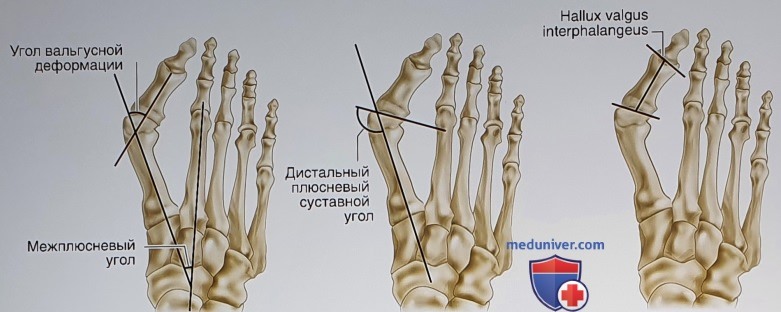

Рентген после операции Hallux valgus